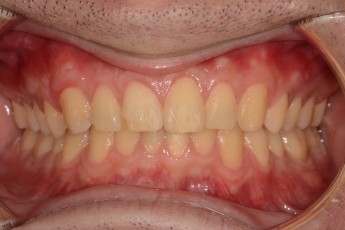

Before

After